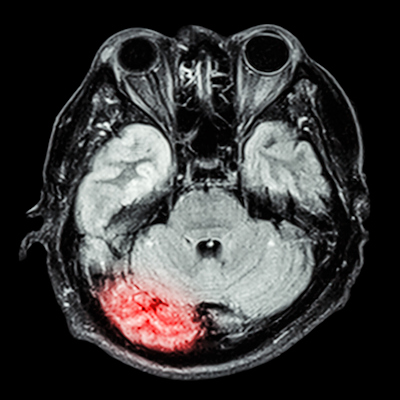

Under an extended partnership, Philips said the companies aim to deliver more standardized and data-driven imaging. NeuroQuant provides quantitative analysis of MRI scans in patients with neurological conditions such as Alzheimer’s disease, multiple sclerosis, and brain tumors.

Integrating quantitative analysis tools directly into the scanners provides clinicians with objective, numerical data alongside images, which enables faster and more consistent diagnoses, Philips added.